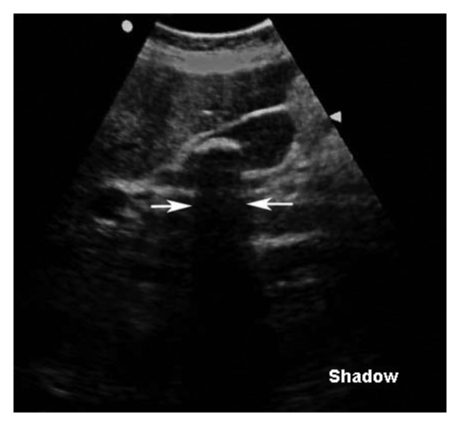

Acoustic shadow seen distal to a high-attenuating structure.